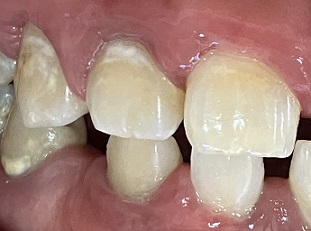

下画像3

重度歯周病 強い歯肉の腫れ